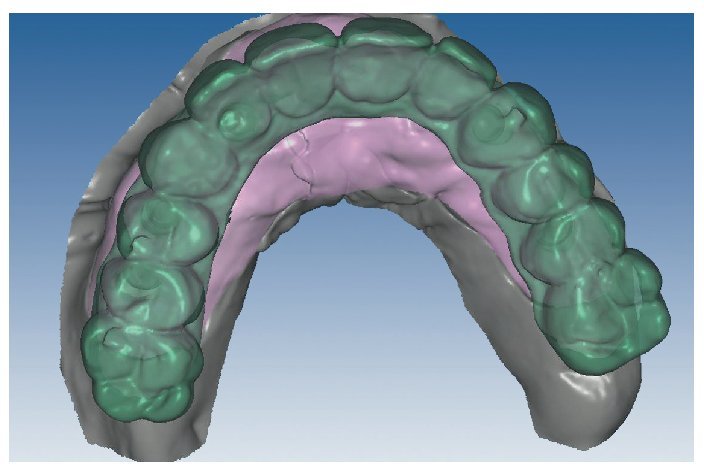

Mediante el uso de un escáner óptico de luz estructurada, los protocolos CAD registran los primeros datos relativos al modelo maestro con las correspondientes posiciones de implante (figs. 87 y 92). En el siguiente paso tiene lugar la digitalización de la planificación, previamente realizada en cera de escaneo matificada, de la restauración definitiva (figs. 88, 90 y 93). La subsiguiente conciliación de los datos mediante el uso del software de diseño dental permite al protésico planificar virtualmente el resto del procedimiento (figs. 89 y 91, 94 a 96) a partir del diseño de las estructuras (figs. 97 y 98).

Fig. 87. Imagen CAD del modelo maestro superior.

Fig. 88. Imagen CAD de la planificación definitiva para el maxilar superior.

Fig. 89. Planificación CAD de la estructura del maxilar superior.

Fig. 90. La posición de los implantes en relación con la planificación.

Fig. 91. El diseño definitivo de la estructura para el maxilar superior.